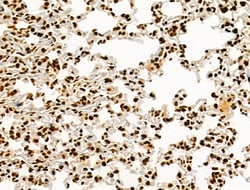

Invitrogen™ Phospho-AKT1 (Ser124) Polyclonal Antibody

Antibody detects endogenous levels of AKT1 only when phosphorylated at Ser124.

| Immunohistochemistry (Paraffin), Western Blot, Immunocytochemistry | |

| A synthesized peptide derived from human AKT1(Accession P31749), corresponding to amino acid residues around phosphorylated Ser124. | |

| Human, Mouse, Rat | |